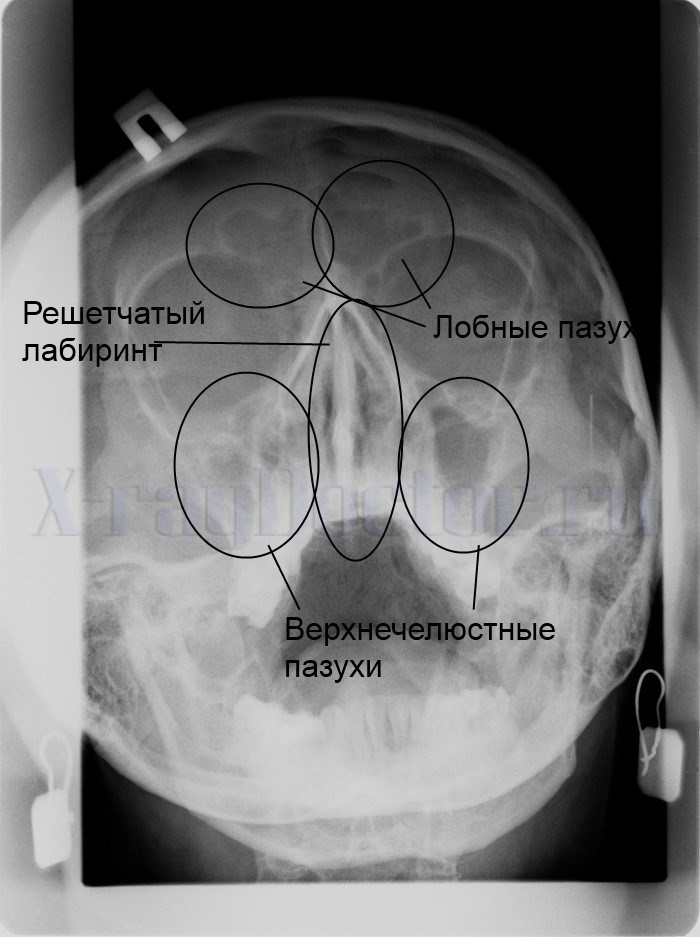

Какие структуры показывает рентген в подбородочной проекции:Такая проекция хорошо показывает решетчатые лабиринты возле носа, которые загрязняются при воспалении одновременно лобных и верхнечелюстных пазух.

Самым сложным при рентгенографии носа является обзор решетчатого лабиринта. Для визуализации данных анатомических образований можно выполнить только передний снимок. На боковой рентгенограмме не будет четко прослеживаться решетчатый лабиринт.

Рентгеновский снимок при гайморите показывает следующие структуры:

- Полость носа.

- Просветления воздушных полостей.

- Орбиты глаз.

- Область затемнения.

- Лобную кость.

- Решетчатый лабиринт.

Рентген позволяет четко проследить нарушение пневматизации носовых полостей, так как скопление жидкости четко прослеживается на рентгенограмме. При анализе структуры решетчатого лабиринта следует обращать внимание не столько на пневматизацию, сколько на четкость контуров каждой ячейки.